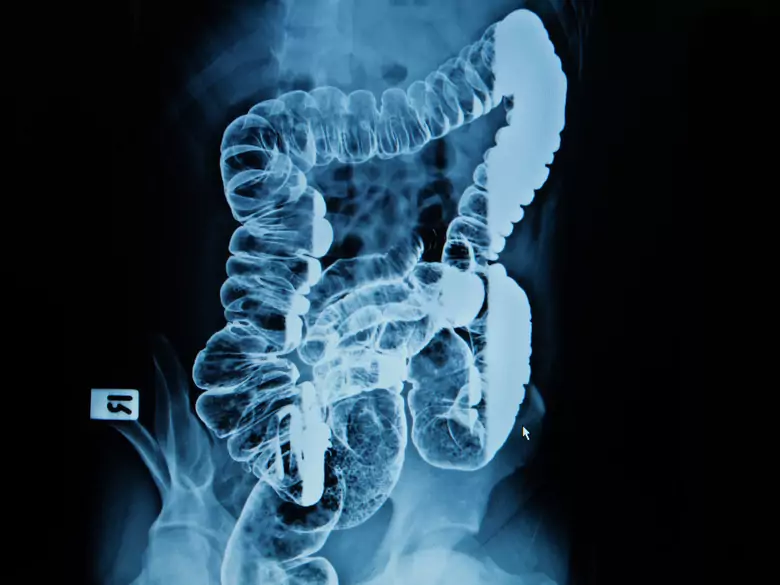

Bowel examination